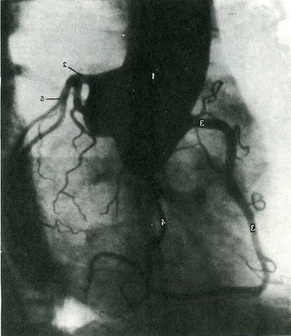

Коронарографія - метод, який дозволяє вивчити прижиттєве стан судин серця. Виконується в спеціалізованих установах. Для виконання коронарограмм необхідні затримка кровотоку через аорту шляхом введення надувного балончика і короткочасна зупинка серця або введення катетера в вінцеві судини. В результаті потрапляння контрастної речовини в серцеві судини на тіні серця будуть видні більш контрастні кровоносні судини. Знімок вважається якісним в тому випадку, якщо заповнені гілки серцевих судин до 3-го порядку галуження як правої, так і лівої вінцевої артерії серця (рис. 392).

392. Коронарографія серця (прижиттєва рентгенограма) (К. Б. Тихонову). 1 - аорта; 2 - ліва вінцева артерія; 3 - права вінцева артерія; 4 - передня міжшлуночкова гілка; 5 - огинаюча гілка.

Знімки роблять у прямій, правої і лівої косих і бічній проекціях.